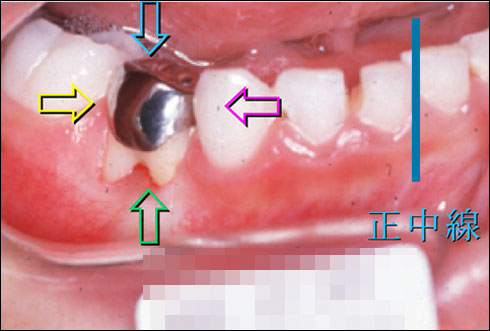

乳歯がなければ!

まわりの乳歯の移動、後継永久歯の変化

乳歯があるから?

何時の間にか乳歯が沈没した?

乳臼歯の骨性癒着による咬合異常

4. 下顎左側第一大臼歯の著しい近心傾斜

5. 下顎左側第二乳臼歯の埋伏低位と後継永久歯胚の位置異常